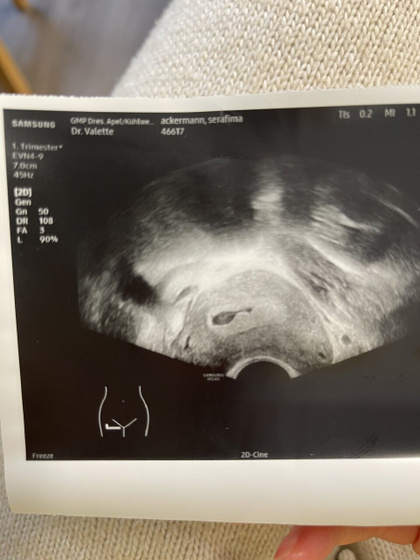

Плодное яйцо вроде есть, но срок ещё конечно катастрофически мал. Если б не рецепты на клексан и утрогест, не поперлась бы конечно Так рано к врачихе…

Все отлично для этого срока ? главное ПЯ уже видно и оно в матке)

9 января был первый день цикла… получается акушерский срок 3 недели 3 дня, плюс у меня была ранняя овуляция, изза этого тест очень рано до задержки показал положительный результат.

Плодное яйцо есть но эмбриона и жёлтого мешка ещё нет

ЖМ видно там. Кружок такой внутри

Конечно есть плодное яйцо и в нем уже тоже видно что, что-то зарождается? а врач что сказал?